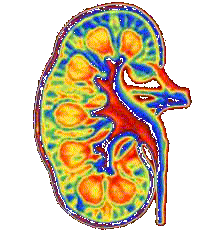

Een N&G-er in hart en nieren heeft grote belangstelling voor het menselijke lichaam. In deze onderzoeksopdracht geven we je de mogelijkheid dieper in te gaan op allerlei zaken die te maken hebben met de nieren.

De nieren hebben een belangrijke functie in de regeling van de water- en zouthuishouding bij zoogdieren. Als je bedenkt dat het lichaam voor tweederde deel uit water bestaat, snap je meteen het belang. De nieren zijn filters waar het bloed langs stroomt. De nieren filteren het bloed van afvalstoffen en vormen de urine. De urine met de afvalstoffen wordt opgeslagen in de urineblaas en via de 'bekende' weg afgevoerd.